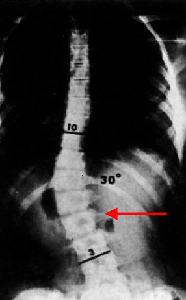

يتم التشخيص بالفحص السريري و الأشعة , و سوف نذكر طريقة قياس زاوية الإنحناء من الأشعة و التي تُسمى طريقة كوب Cobb Method و كذلك يُطلق على الزاوية زاوية كوب Cobb Angle . و تُقاس من صورة الأشعة السينية بالطريقة التالية:

" تعيين الفقرات التي تحدد الطرف العلوي و الطرف السفلي للإنحناء. و هذه الفقرات هي أشد فقرات الإنحناء ميلاناً تجاه الجهة المُقعرة للإنحناء.

" بعد تعيين الفقرتين , يُرسم خط مستقيم يمر بالطرف العلوي للفقرة العلوية للإنحناء و خط مستقيم آخر يمر بالطرف السفلي للفقرة السفلية للإنحناء.

" تُحسب الزاوية التي تقع عند تقاطع هذين الخطين و هي زاوية الإنحناء.

على اليمين صورة أشعة سينية X-Ray تبين كيفية حساب درجة زاوية إنحناء الجنف (زاوية كوب Cobb Angle) , الزاوية b هي زاوية الإنحناء و تساوي الزاوية a , و تساوي 70 درجة. على اليسار صورة لأشعة مقطعية محوسبية (بالحاسوب) Computerized Tomographic Scan CT و حساب الزاوية بالكمبيوتر.